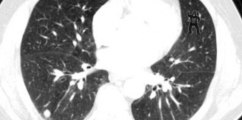

AI could be deployed in breast cancer scans, research finds

Artificial Intelligence could be deployed in breast cancer scans, researchers in Sweden's Lund University find.